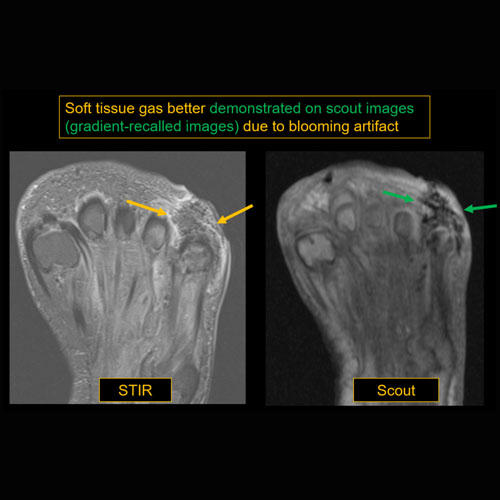

There is gas or foreign body. |

Yes | NA |